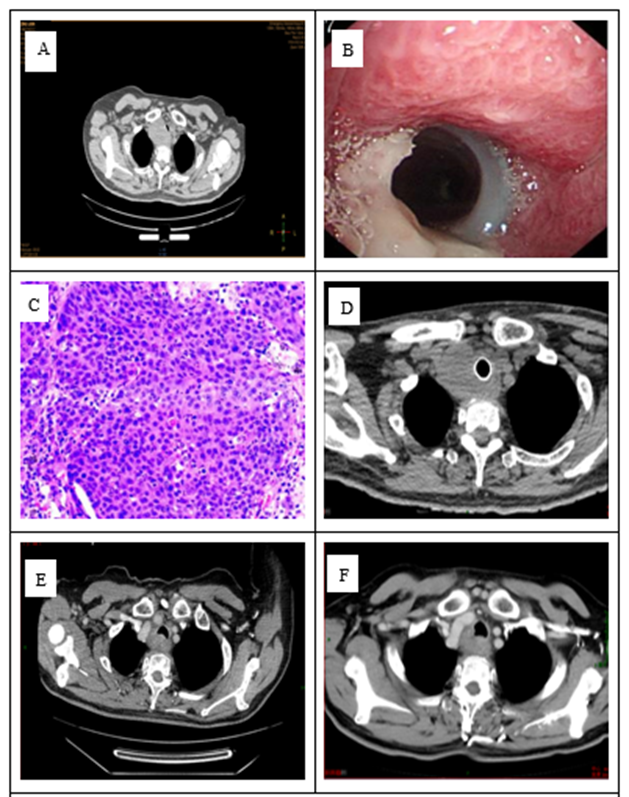

Case 1: A 59-year-old male patient presented to an external hospital for "cough, hoarseness, and shortness of breath for 1 month." He has a 30-year history of smoking and no history of cardiothoracic surgery or tuberculosis. Cervicothoracic CT revealed a mass in the soft tissues adjacent to the trachea at the thoracic inlet, tracheal stenosis, and a mediastinal mass. Bronchoscopy showed new growth in the membranous part of the airway, spanning zones I-II (intraluminal, mural, and extramural components), with luminal stenosis of approximately 80%. Carbon dioxide extraction identified some newly detected organisms, and a pathological examination was conducted. After cauterizing the tumor with an argon beam, a rigid endoscope was used to place a stent in the airway spanning zones I-III. After treatment, the lumen was wider than before, with stenosis reduced to approximately 40%. Our hospital's pathological consultation confirmed high-grade squamous cell carcinoma, but the sample was insufficient for PD-L1 testing. Pulmonary infection occurred 3 days post-operation and improved with symptomatic treatment. A whole-body 18F-FDG PET-CT scan showed that the tracheal stent had changed, occupying space on the right side of the trachea and was considered malignant. Multiple lymph node metastases were noted in the 1L, 2R, 4R, and 4L areas of the mediastinum. The diagnosis was primary tracheal squamous cell carcinoma with mediastinal lymph node metastasis. The clinical stage was cT4N1M0, stage IV, as defined by the Bhattacharyya criteria [5].ECOG: 1 point. The patient received chest volume rotational intensity-modulated radiation therapy from October 2023 to December 2023, with the following prescription doses: 95% PGTV: 60.2 Gy/2.15 Gy/28 fractions, and 95% PTV: 50.4 Gy/1.8 Gy/28 fractions. Radiotherapy was paused for 3 weeks due to a lung infection during treatment, and the bronchial stent was removed during the pause. Synchronous chemotherapy was administered for two cycles during radiotherapy, consisting of albumin-bound paclitaxel plus carboplatin. During treatment, Grade I anemia and Grade II esophagitis occurred, which improved with symptomatic treatment. Concurrent chemoradiotherapy was followed by durvalumab immunotherapy maintenance. Follow-up until June 2025 showed no tumor progression for 18 months (Figure 1).

Figure 1: A: CT at diagnosis; B: Endoscopic stent placement; C: Pathological HE × 200; D: Post-stent placement CT; E: CT one month after radiotherapy completion; F: CT four months after radiotherapy completion.